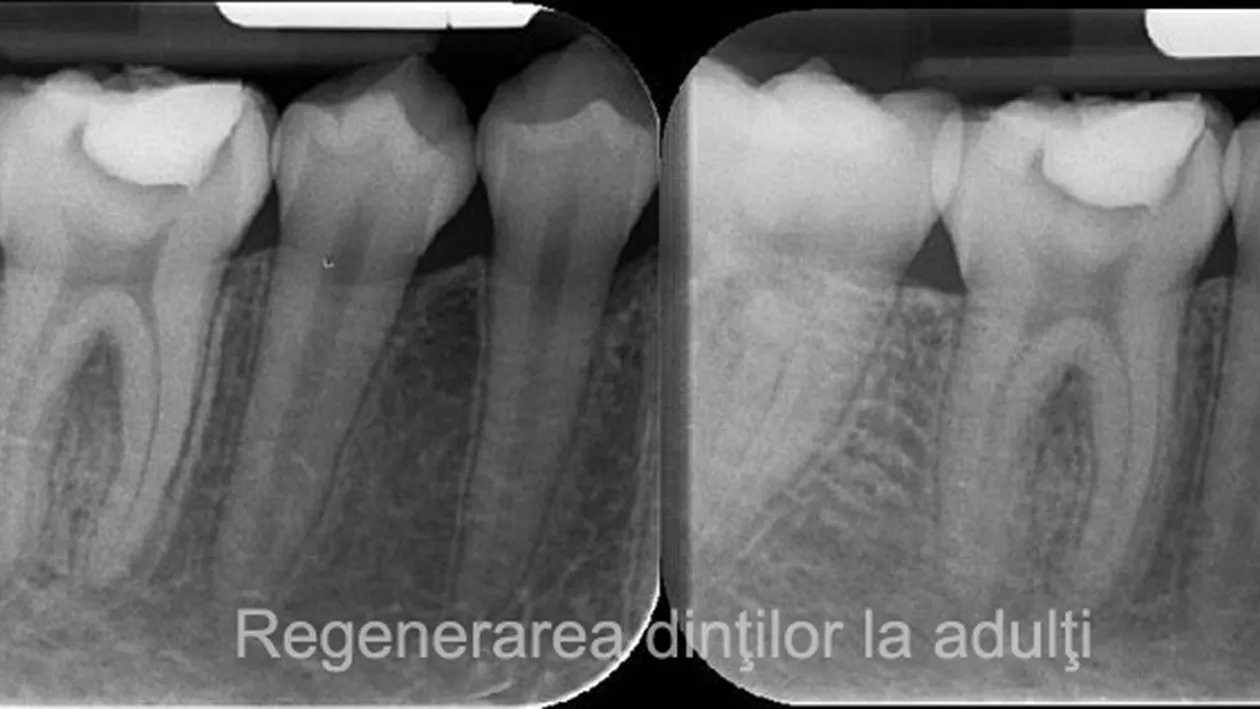

Dezvoltat și testat pentru a trata boala Alzheimer, medicamentul se întâmplă, de asemenea, să ajute mecanismul natural de regenerare a dinților. Tideglusib funcționează prin stimularea celulelor stem din pulpa dinților, sursa de dentină nouă. Dentina este substanța mineralizată sub smalțul dintelui și distrusă de cariile dentare.

Dinții pot regenera în mod natural dentina, fără asistență, dar numai în anumite circumstanțe. Pulpa trebuie expusă prin infecție, cum ar fi degradarea, sau traume pentru a determina fabricarea dentinei. Dar chiar și atunci, dintele poate să redea doar un strat foarte subțire (nu este suficient pentru a repara cavitățile cauzate de carii, care sunt în general adânci). Tideglusib modifică acest rezultat, deoarece împiedică GSK-3, care oprește formarea dentinei.

O echipă de cercetători a testat medicamentul pe șoareci, tratând cariile acestora cu un burete de colegan biodegradabil, îmbibat in tideglusib. În timp, buretele s-a dezintegrat, fiind înlocuit de dentină, dintele reparându-se de la sine. Deoarece această metodă încurajează corpul să se vindece singur, poate să elimine o mulțime din problemele legate de tehnicile actuale.